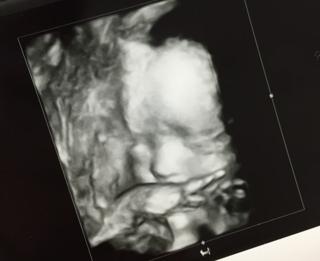

写真:24w5d:あおちゃさん:ママのお腹をキック!

顔の前に手を伸ばしたりしていて可愛かったです!!

頭、お腹、脚全て1週間分程大きく推定体重は839グラム! 特に脚がかなり長い(°_°)♡ 鼻の形と口は旦那似で鼻の高さは私似かな?(^^) 3人目にして初の女の子♡ 旦那に似てガタイのいい子になりそうな予感、、、笑 4Dエコーでは指しゃぶりしたりあくびをしたり、ニコッと笑ったりして可愛かった(o^^o) 上2人ともえくぼがあるのですが、この子にもありそうな感じでした!

久々に3D。心なしか微笑んでるようにみえる。とってもかわいい この日はスクリーニングエコーをして、胎児を詳しく見たんだけど、見えないところがあるからまた来週にもう一度見ることになりました。

4D撮ってもらいましたあ!!お顔がよくみれてよかったあ。めちゃくちゃ可愛い!!あっ。ちなみに男の子です。早く会いたいよ~。